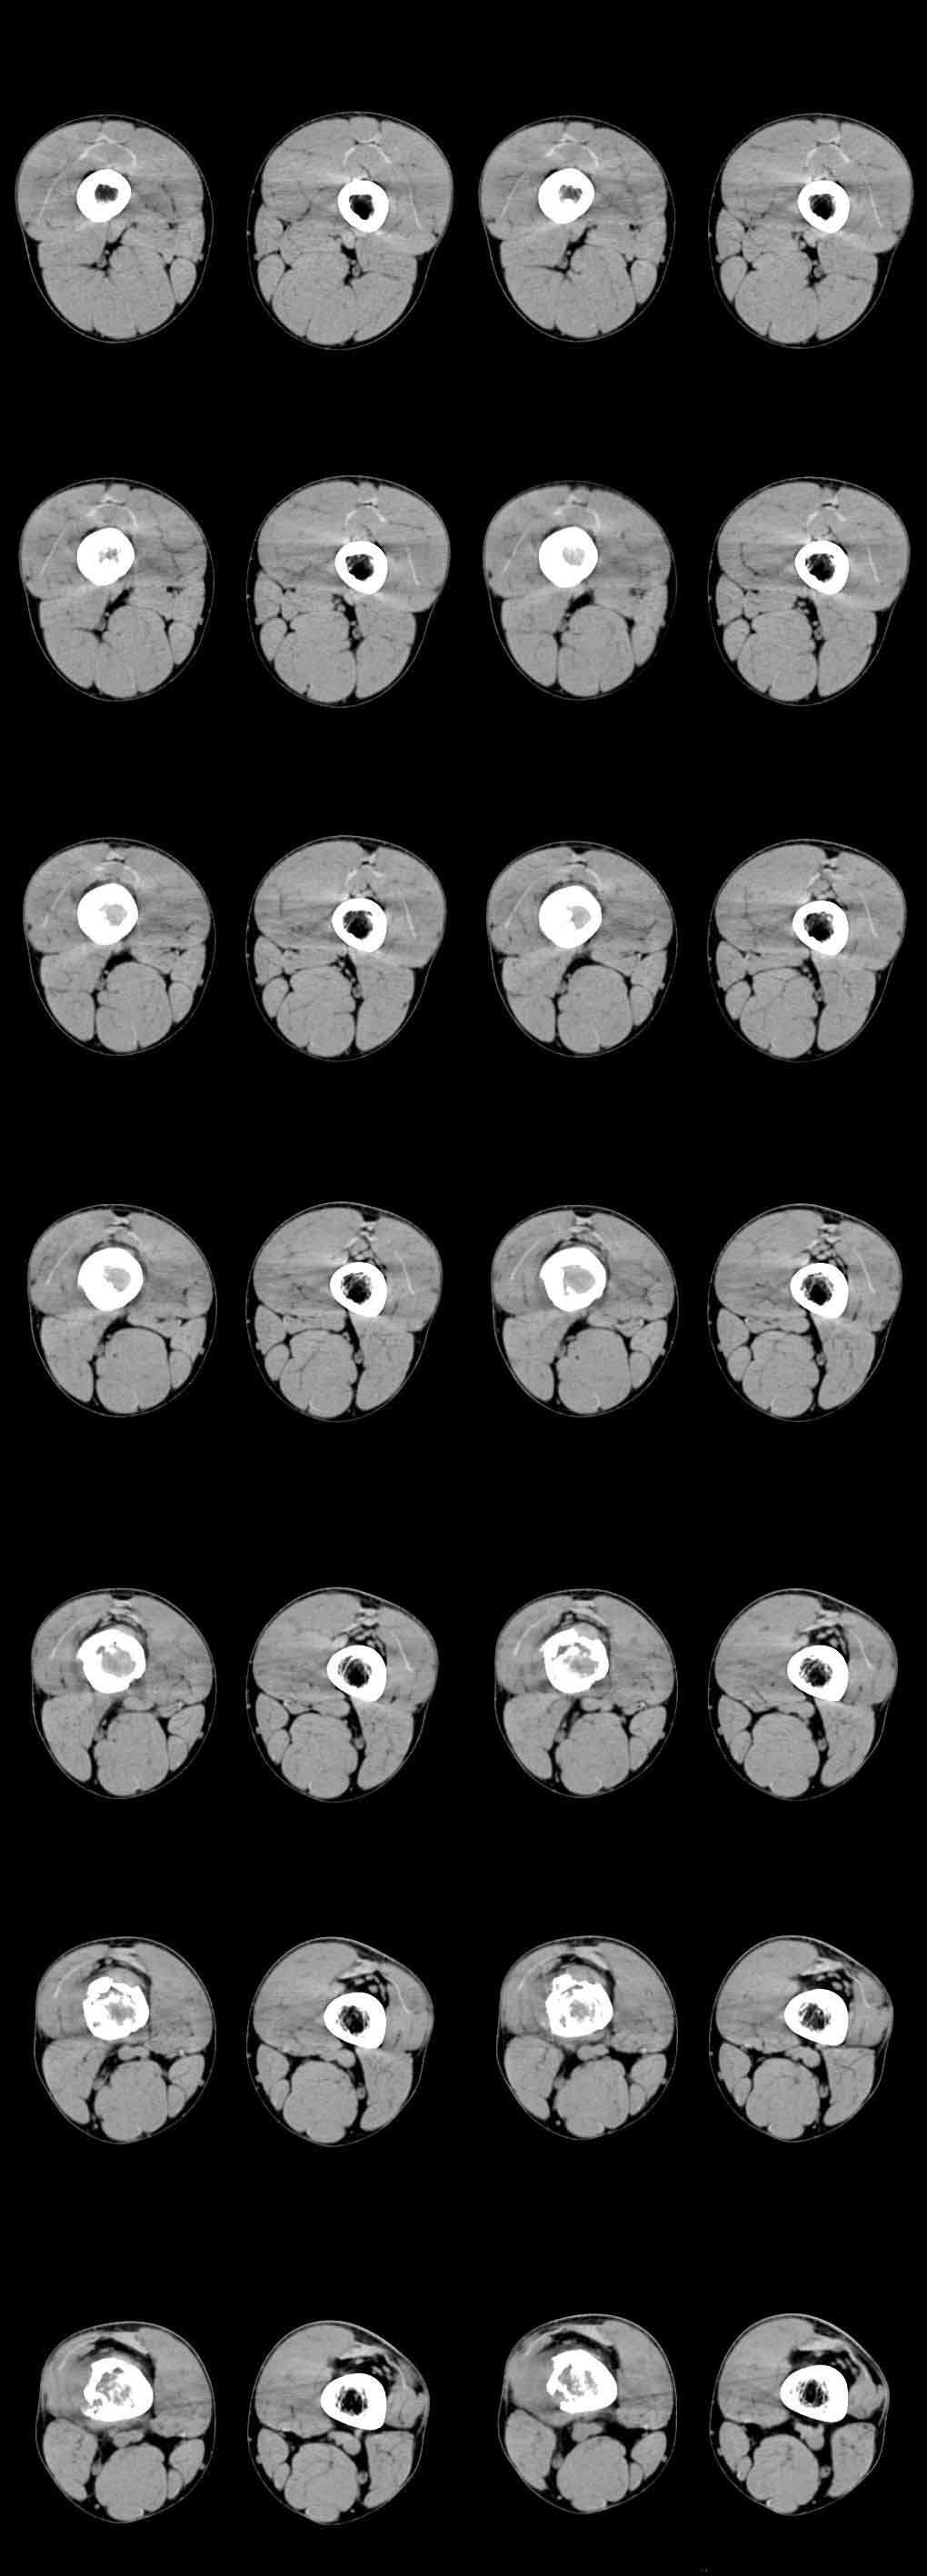

患者年龄、发病部位、ct表现:溶骨性骨质破坏、柳絮状肿瘤骨形成、骨膜增生、软组织肿块(虽然小)

都支持骨肉瘤的诊断,能够上传x线片就好了。

x线对骨膜反应及骨膜三角显示好,建议上传平片。同意骨肉瘤诊断(ct对骨质破坏,肿瘤骨及软组织肿块显示较好)。